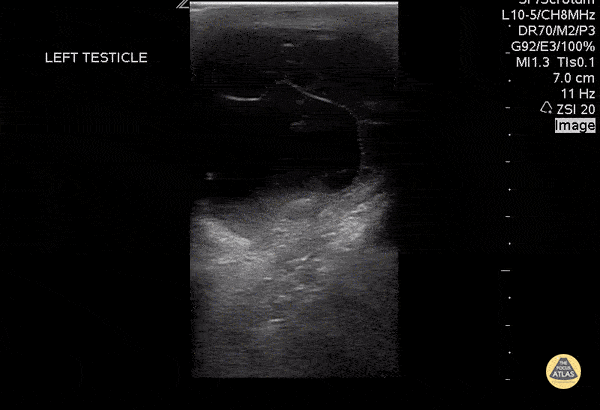

A 30 year old sexually active male with no previous medical history presented to the emergency department with testicular pain. POC US demonstrates a septated hydrocele. Mario Corro, MD, PGY-3 Staten Island University Hospital